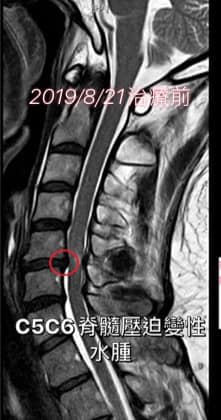

Cervical Spine Treatment Cases 頸椎治療案例 #特殊案例頸椎手術後又再度突出案例 #感謝台中劉大哥熱情見證 #親自手捏醫師娃娃公仔... 2020.11.18 #頸椎病居然會導致手快速萎縮 #脊髓型頸椎病案例 #感謝高雄王大哥熱情見證 #頸椎整合... 2020.11.13 #神經根型頸椎病讓人痛到無法入眠 #感謝新店陳小姐熱情見證 #患者的疼痛日誌讓人感動 ... 2020.11.11 #左邊膏肓長期刺痛案例原來是頸椎病 #之前一直當作肩關節問題處理沒效 #高濃度葡萄糖... 2020.11.03 #腰椎整合醫案逆轉勝 #曾經大痛到無法走路 #坐骨神經痛就是那們痛 #感謝桃園蘆竹張小... 2020.10.29 #特殊案例之味覺錯亂 #原本香甜奶油車輪餅患者覺得酸臭 #按照頸椎病治療五次後突然味... 2020.10.27 頸椎病產生的嚴重交感神經症狀 治療前後比對 2020.10.23 #等待快一年的頸椎受傷醫案追蹤 #頸椎脊髓損傷導致左邊手麻合併下肢無力患者 #前後一... 2020.10.14 #最複雜多變最痛苦難受的頸椎病 #多年的胸悶與心悸伴隨呼吸困難 #交感神經型頸椎病 #... 2020.10.13 #頸椎曲線弧度非常重要 #頸椎弧度有可能逆轉嗎 #短短三個月時間看到效果 #患者超認真... 2020.10.09 #打壘球居然腳不聽使喚跑不起來 #更恐怖的是勉強跑起來還無法剎車 #洗頭往後仰身體背... 2020.10.07 #疼痛三年頸椎病患者親手寫下治療紀錄 #交感神經型頸椎病 #症狀錯綜複雜 2020.10.02 #困擾四年多胸悶手麻頭暈醫案 #一切原因居然是頸椎出問題 #交感神經型頸椎病症狀錯綜... 2020.09.11 #交感神經型頸椎病引起的耳鳴 #耳鳴將近八個月終於得到重大改善 #曾經耳鳴到無法睡覺... 2020.08.22 #感謝板橋蘇先生熱情見證 #神經根型頸椎病卡壓 #曾痛痛到左手無法騎單車撥桿 #麻脹刺... 2020.08.04 ← 上一頁 4 5 6 7 8 下一頁 →